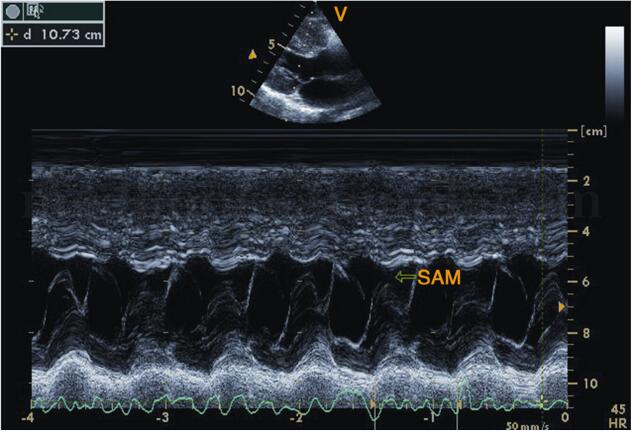

超声可以评估二尖瓣前叶的活动,反应sam征,以了解左室流出道梗阻情况

5,收缩期可见二尖瓣前瓣前向运动,即sam征,部分患者可因此合并二尖瓣

5 平方厘米 室间隔明显增厚者,二尖瓣可出现sam征,心尖区可闻及收缩

二尖瓣sam征M型示意图